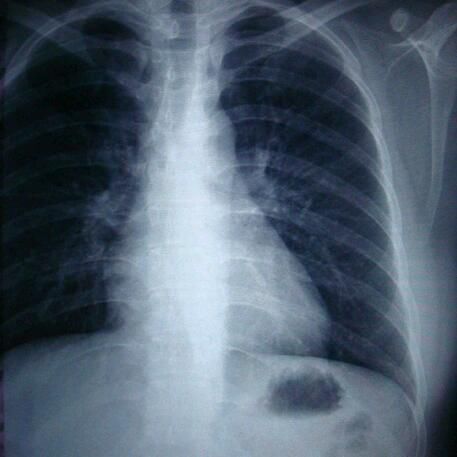

那是胸

这是磁共振和ct都有吧